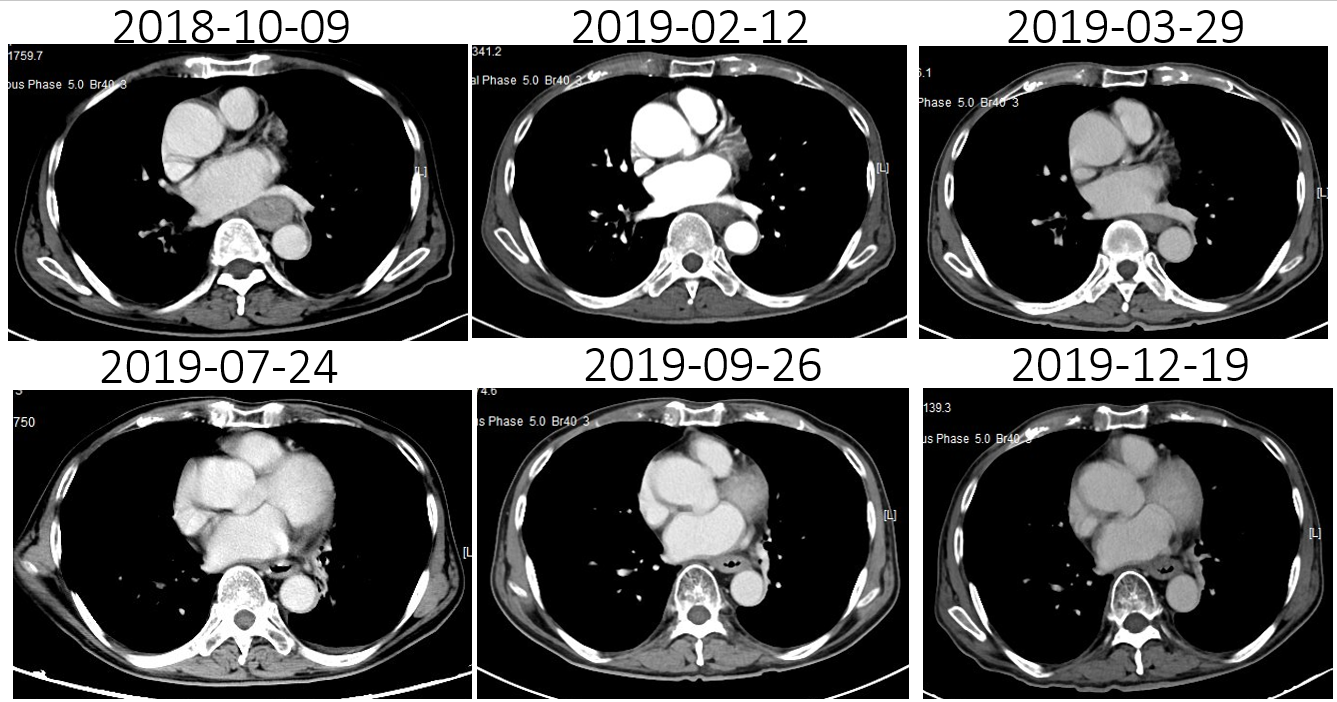

(4)2019-07-24复查CT:腹腔肿大淋巴结较放疗前缩小

(5)2019-09-26复查CT:腹腔肿大淋巴结较放疗后增大,出现左上腹痛

(9)12-19复查CT:腹腔淋巴结较09-26日缩小,3疗程“雷替曲塞 durvalumab“治疗评估达PR。